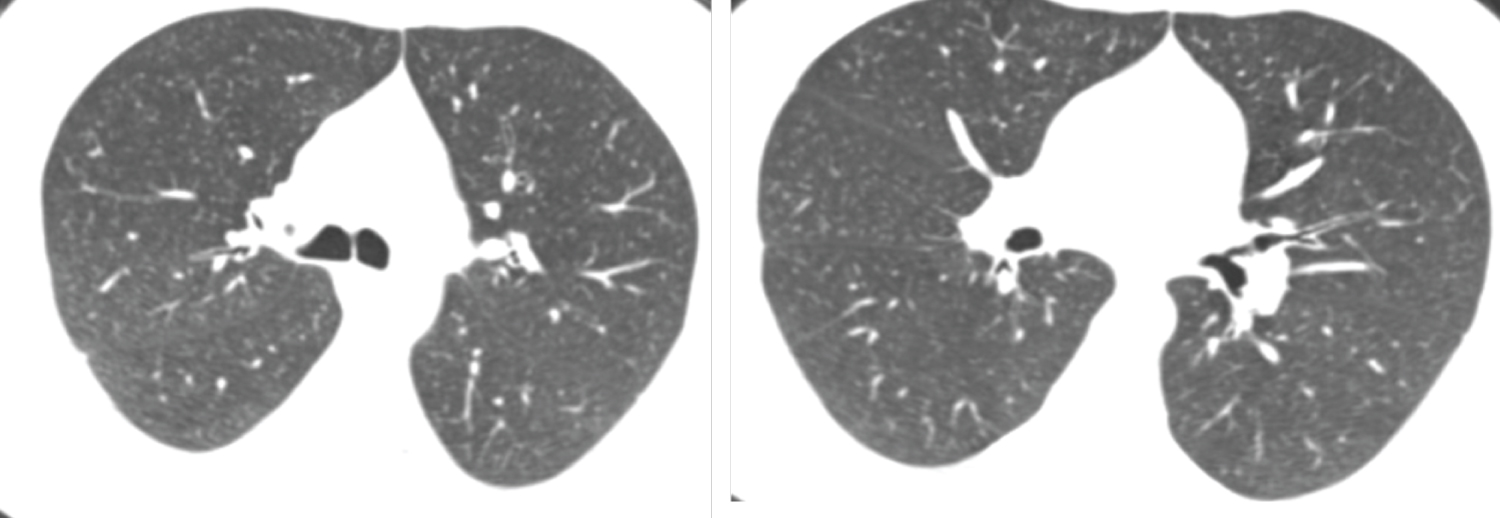

Figure 2: Male patient aged 49-years-old had negative initial reverse transcription-polymerase chain reaction results. Axial CT chest cuts show bilateral decreased both lung attenuation with increased both lung volumes denoting hyperinflation associated with bilateral upper lobe fine centrilobular ground glass nodular infiltration suggestive of smoking related bronchiolitis (respiratory bronchiolitis) (CORADS 1). View Figure 2

Figure 3: Female patient aged 56-years-old had positive initial reverse transcription-polymerase chain reaction results. Axial CT chest cuts show two patchy areas of consolidation with air bronchogram within are seen at middle lobe of right lung and right lower lung lobe these findings are unclear for COVID-19 (CORADS 3). View Figure 3

Figure 4: Female patient aged 37-years-old had negative initial reverse transcription-polymerase chain reaction results. Axial CT chest cuts shows bilateral ill-defined ground glass opacities with peripheral & sub-pleural in distribution seen at both upper and lower lung lobes these findings are highly suspected for COVID-19 (CORADS 4). View Figure 4